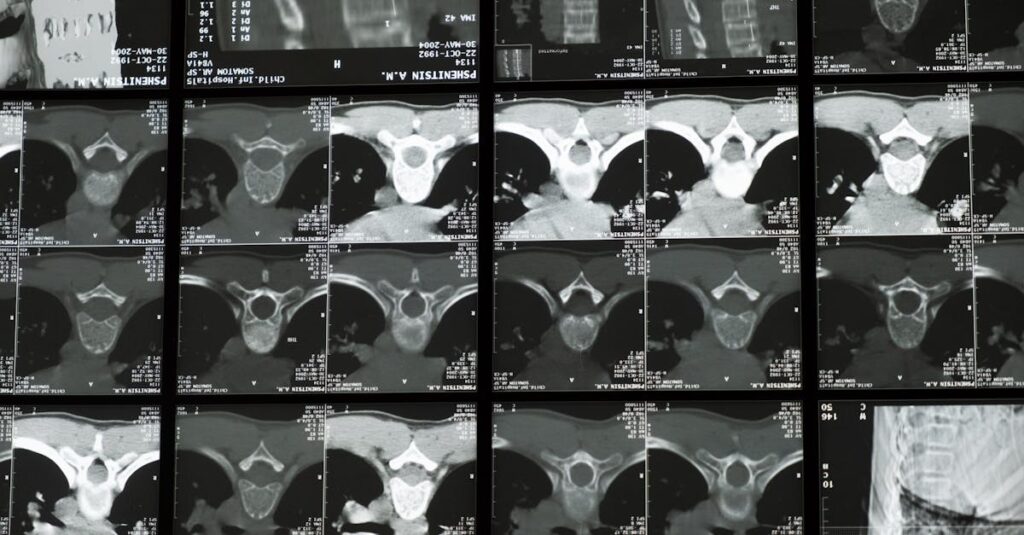

Décompression neurovertébrale : études cliniques sur l’arthrose